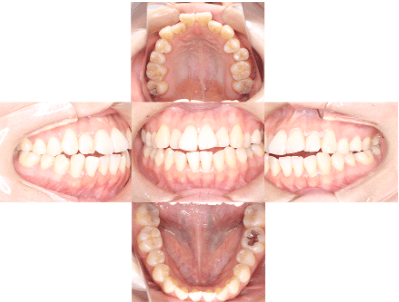

治療後

• 初診時年齢:25歳

• 主訴:開咬

• 診断:舌癖を伴う歯性の開咬

• 抜歯箇所:非抜歯

• 治療内容:下で前歯を押してしまい、前歯で咬めない状態でした。マウスピース型カスタムメイド矯正歯科装置(製品名インビザライン 完成物薬機法対象外)で、奥歯を低くしつつ、前歯を伸ばし、前歯で咬めるようになりました。

• 治療期間:2年6ヶ月

• リスク:ブラックトライアングル(歯と歯の間と歯ぐきの間の三角形の隙間)が強くでる場合がある

• 費用:99万円